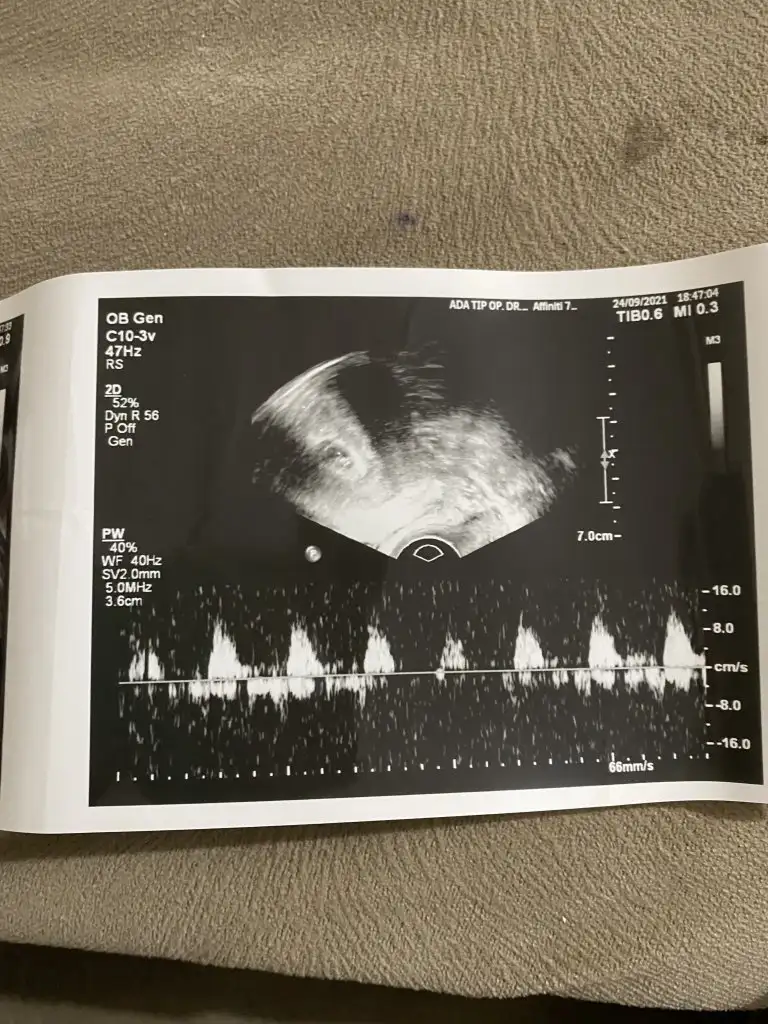

Selamlar herkese 5+5 haftalık bebişim. vajinal bakıldı.sizce kızmı erkek mi

Banada tahminde bulunabilecek biri var mı vaginal usg

Ramzi teorisine göre ( bilimsel bir araştırma sonucuymuş ve %85 doğruluğu varmış). İlk 6-8 haftalık ultrason görüntüsüne göre bebeğin kesenin içersinde soldan ya da sağdan girişine göre cinsiyet tahmini yapılıyor. Bilimsel olunca tecrübeli annelerimiz yada anne adaylarımızdan yardım istiyoruz. Doğruluğu var mı öğrenmek adına :) Bizleri aydınlatırsanız çok seviniriz. bu teorieye göre;

Vajinal muayeneyle bakıldıysa eğer;

Sağdan girmiş gözüküyosa aslında solmuş ve ERKEK,

Soldan girmiş gözüküyosa aslında sağmış ve KIZ ,

Karından bakıldıysa eğer,

Soldan girmiş gözüküyosa gerçektede solmuş ve ERKEK,

Sağdan girmiş gözüküyosa gerçekte de sağmış ve KIZ,